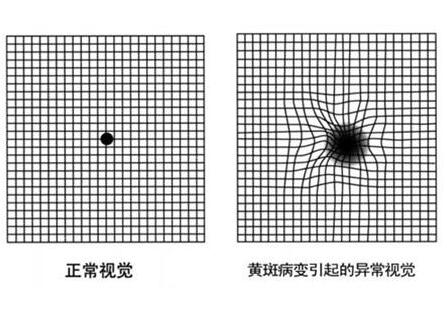

黄斑前膜